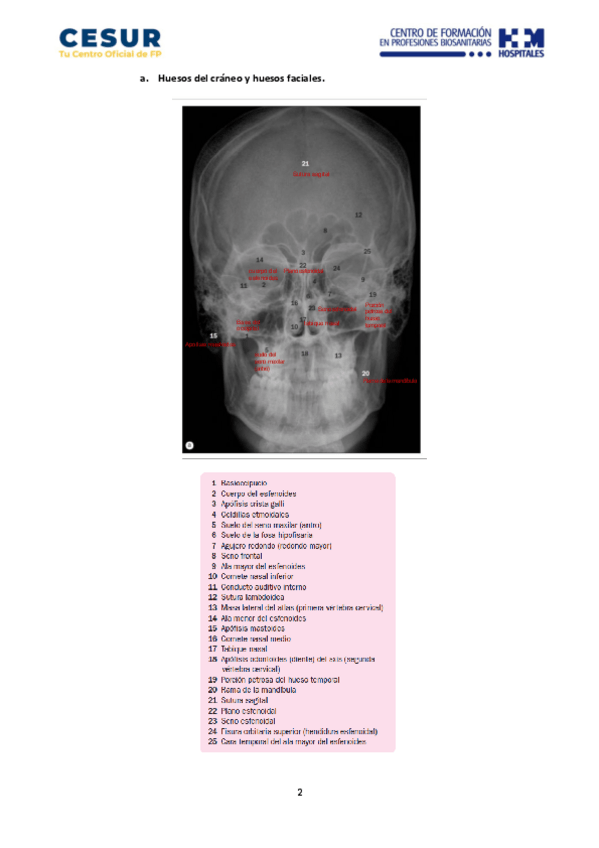

He publicado nuevos apuntes de Anatomía por la Imagen: Ejercicios-1.-Reconocimiento-de-imagenes-de-los-huesos-de-la-cabeza.pdf